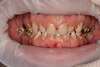

3- Les couronnes pour restaurer, en combinaisons avec les implants des situations complexes

Il est possible de corriger des situations pathologiques liées à une usure importante des dents.

Là aussi un diagnostic complet et une prévisualisation du résultat final est nécessaire avant d'entamer le traitement (WAX UP)